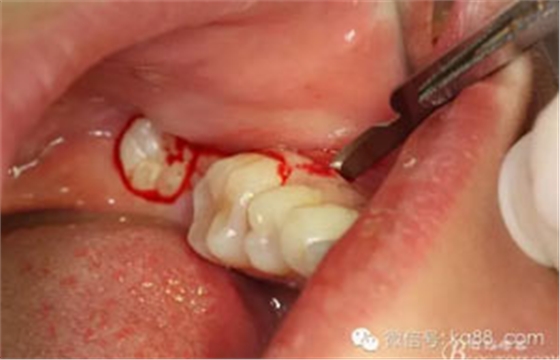

圖11.去骨逐漸暴露37牙冠

圖12.去骨完成、露出37牙冠。